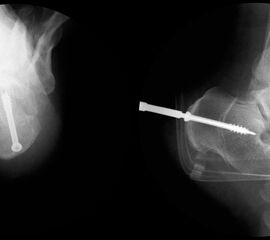

Röntgenaufnahmen des Fußes d.p., streng seitlich und schräg unter Belastung. Saltzmann Aufnahme zur Beurteilung der Rückfussachse.

Operationsplanung anhand der Röntgenaufnahmen unter Beachtung wichtiger radiologischer Landmarks wie Rückfussachse, Metatarsale I – Talushals-Achse im dp und lateralen Strahlengang (Abbildung 1 und 2).

Abbildung 1

Abbildung 2